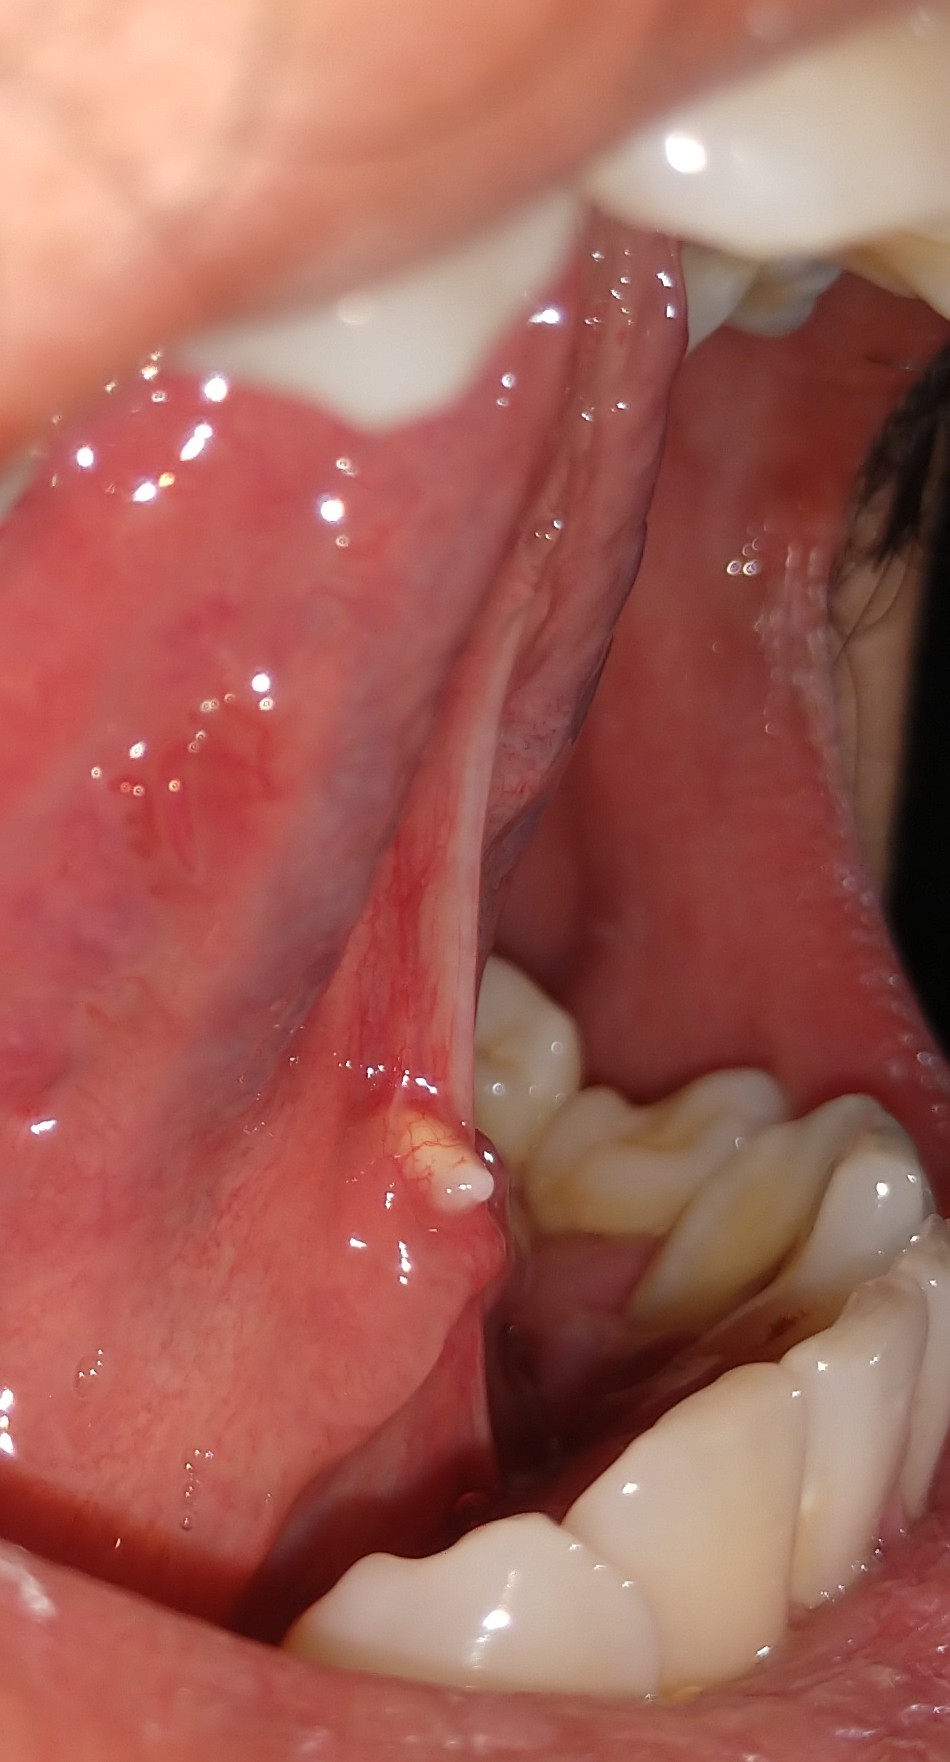

มีติ่งโผล่ออกมาไต้ลิ้นเป็นเพราะอะไรครับ

สวัสดีครับ ขออภัยที่รูปมันไม่สุภาพนะครับ มีไครเคยเป็นแบบนี้มั้งมั้ยครับสังเกตุเห็นมา2วันแล้ว

มันเกิดจากสาเหตุอะไรครับ ตอนนี้รู้สึกกังวลมากแต่ว่ายังไม่มีเวลาไปหาหมอ *ขอบคุณสำหรับคำตอบครับ